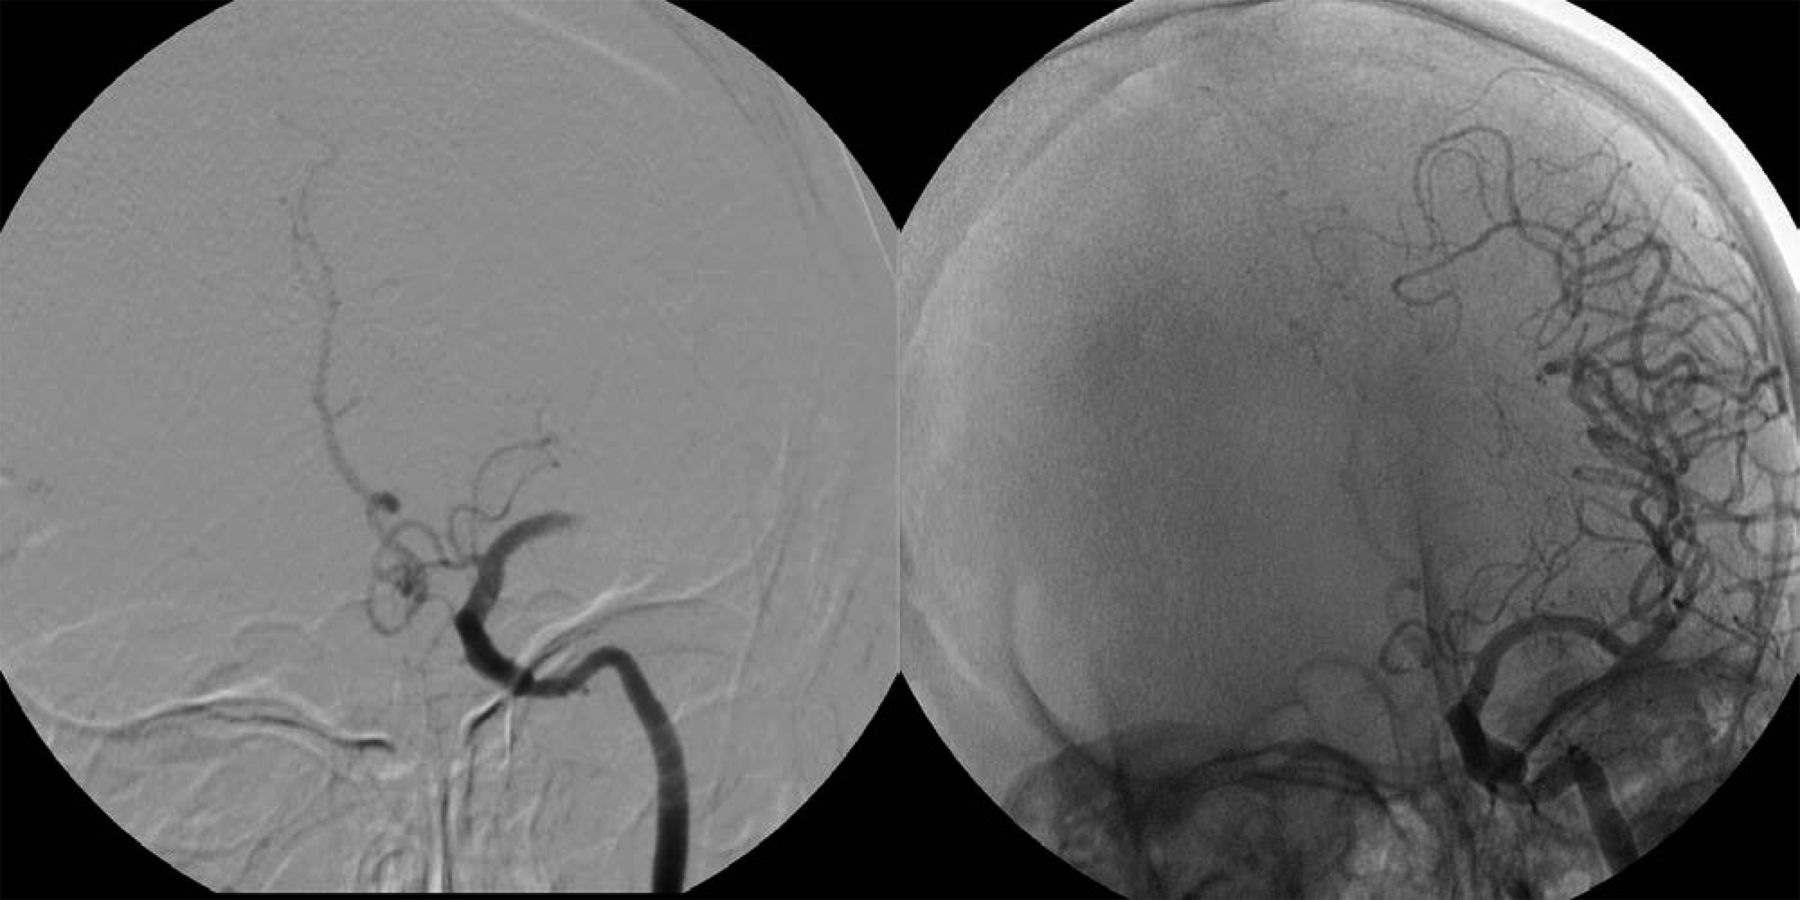

尽管改善功能结果在中风患者接受静脉rtPA,大量的病人(57%对58%)死亡或产生依赖性,尽管治疗。13,16,50,51这促使搜索更好的药物和交货方式,实现更高的血管再通和更快的利率以最小的风险病人。IA溶栓包括高浓度的溶栓药物管理局在血栓附近,利用低剂量比系统性管理。这可能会导致降低系统性并发症,包括颅外的出血(图2),减少当地的这些药物神经毒性的影响。5这种方法还允许同时使用的机械设备,以促进溶栓(图3)。5,52,53结合IA交付与机械血栓切除术增加了表面积暴露在溶栓药物(图2)。IA形态的缺点包括潜在的延迟要求获得的初始脑血管造影术和位置microcatheter溶栓的管理代理。这些问题导致了IA的倡议提供静脉溶栓后溶栓。中风的应急管理(EMS)桥接试验,随机,双盲,安慰剂对照设计,展示了更高的血管再通率(53%),结合IV / IA比IA溶栓组溶栓治疗组(28%)。54没有差别在两组之间的临床结果和出血症状率无显著差异。这表明联合治疗的可行性。虽然在一些中心IA的做法是受欢迎的一个子集的患者将有限反应输液治疗,包括那些患有严重神经赤字,这些展示3至6小时的症状出现,那些有历史的大手术前两周内,和那些主要颈或颅内血管的阻塞,这在对照试验还有待证明。51

左侧颈内动脉注射了完整的大脑中动脉闭塞M1段(溶栓在脑缺血得分(TICI) 0),治疗动脉内的重组组织纤溶酶原激活物总共22毫克,完全再通(TICI 3)和几乎完全临床改善的NIH卒中量表评分2。